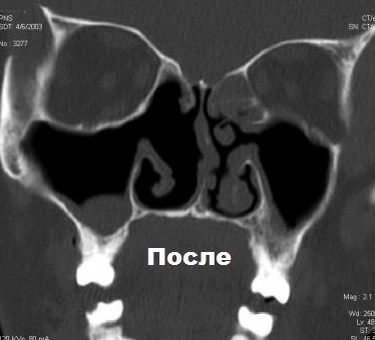

В двух последних многоцентровых исследованиях зафиксировано положительное влияние биопрепарата омализумаба в отношении не только стабилизации течения бронхолегочной патологии, но и купирования основных назальных симптомов полипозного риносинусита. После 16 недель подкожного введения омализумаба у больных полипозным риносинуситом в сочетании с тяжелой аллергической астмой по сравнению с пациентами, получавшими плацебо, зафиксировано достоверное уменьшение распространения полипозного процесса в полости носа и околоносовых пазухах по данным эндоскопического исследования и результатам компьютерной томографии околоносовых пазух. Кроме того, с помощью опросников установлены значимое улучшение качества жизни больных, улучшение обоняния и снижение степени выраженности заложенности носа, выделений из носа и проявлений отдышки. Помимо этого использование омализумаба способствовало снижению частоты назначения пациентам системных гормональных препаратов и антибактериальных препаратов.